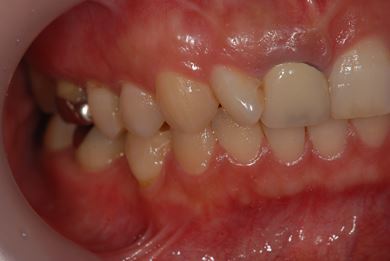

| 性別/年齢 | 女性 / 38歳 | ||||||||||||||||||||||||||||||||

| 主訴 | 右奥歯2本、インレーの相談をしたい。 | ||||||||||||||||||||||||||||||||

| 治療方針 | セラミック治療にて、審美的回復を行う。 | ||||||||||||||||||||||||||||||||

| 治療内容 | ハイブリッドセラミックインレー2本、メタルボンドセラミッククラウン2本(メタルボンド用土台2本)、オールセラミッククラウン1本(オールセラミック用土台1本) | ||||||||||||||||||||||||||||||||